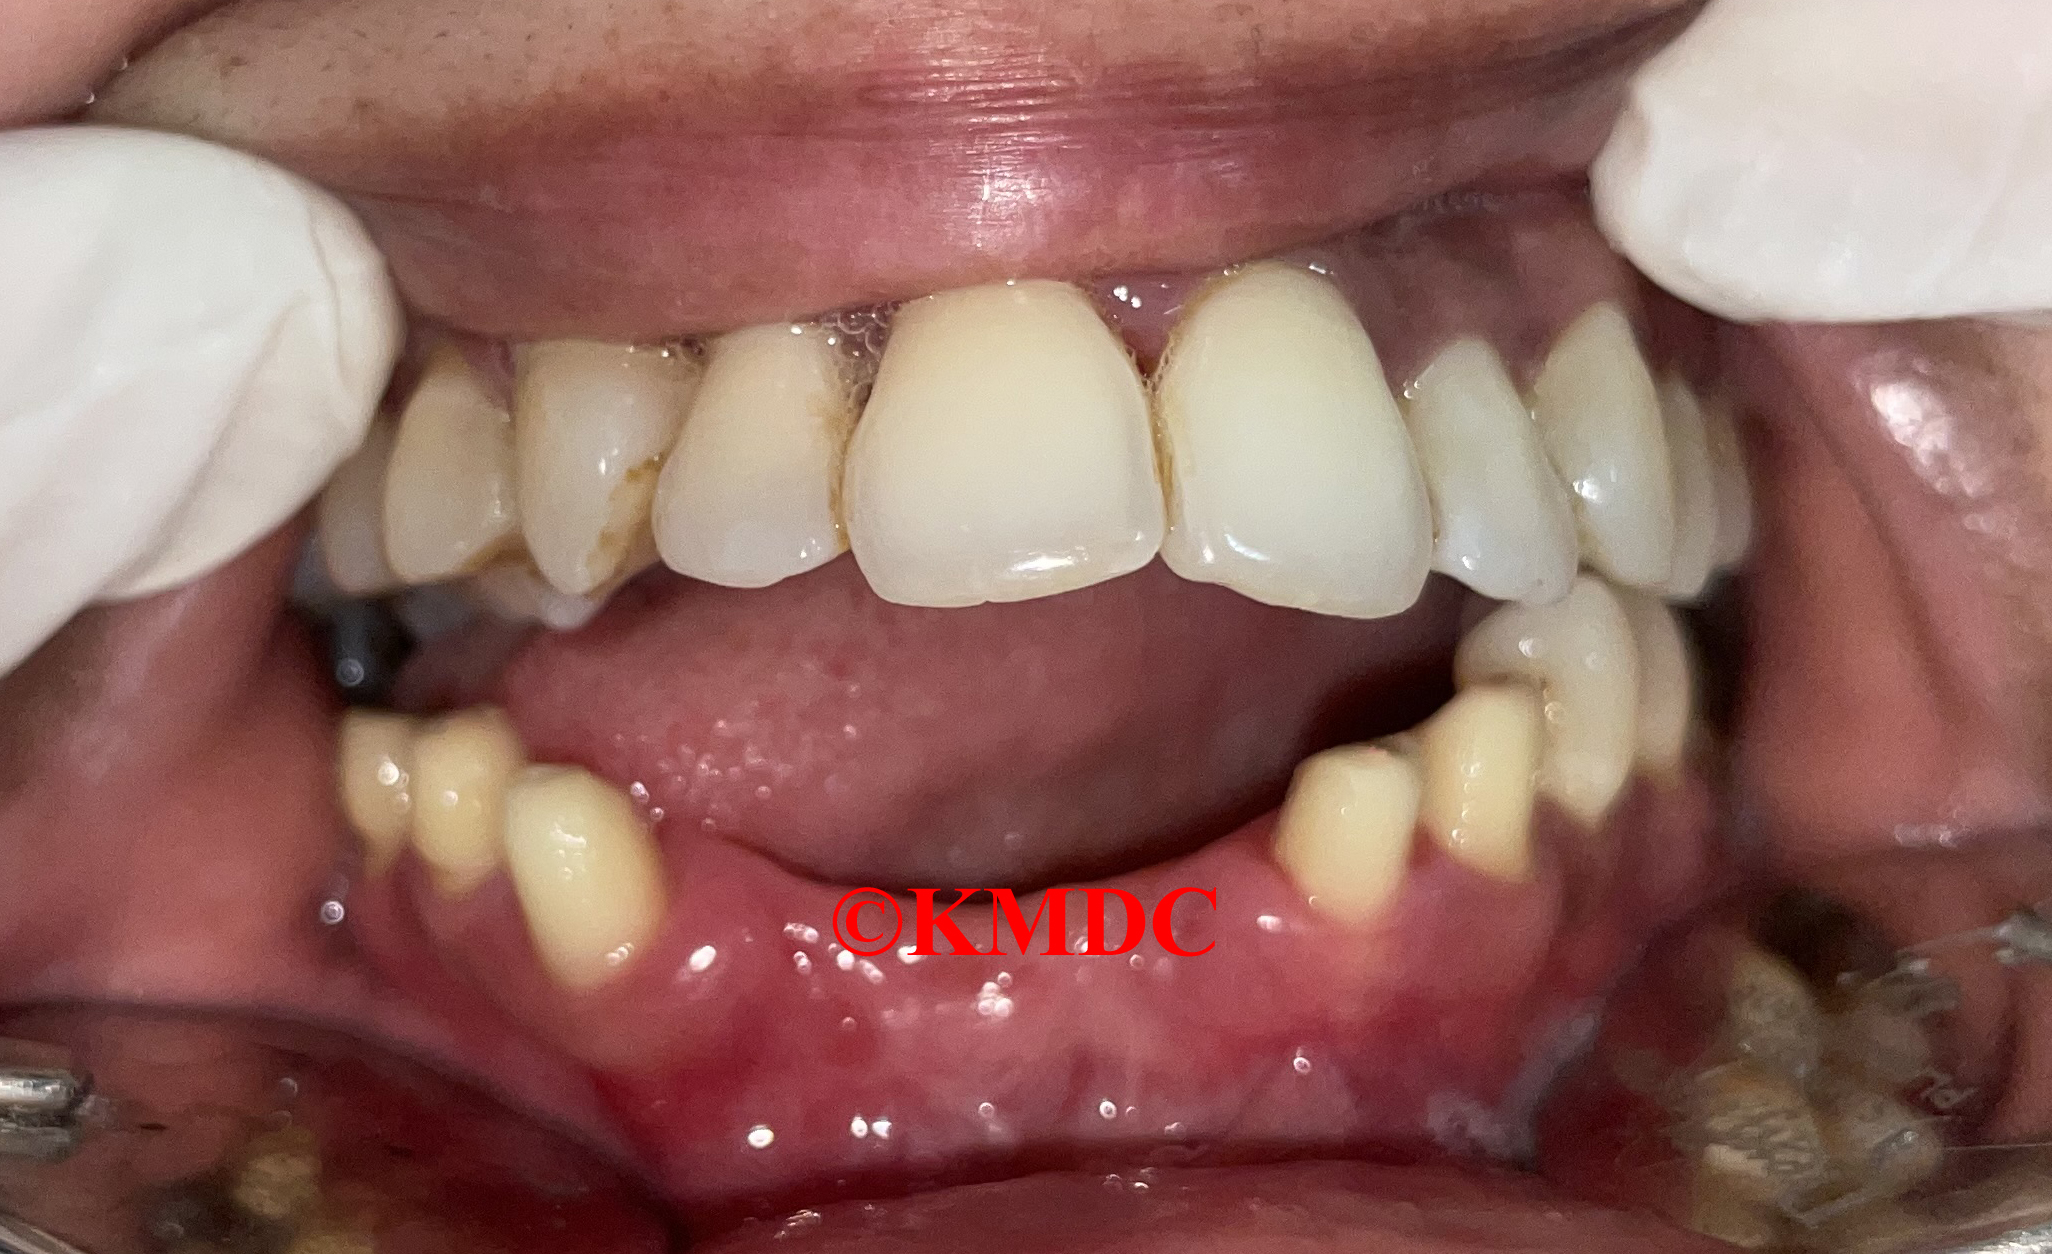

Our Success Stories

Real cases, real results. See how we transform smiles every day.

Clinical Gallery